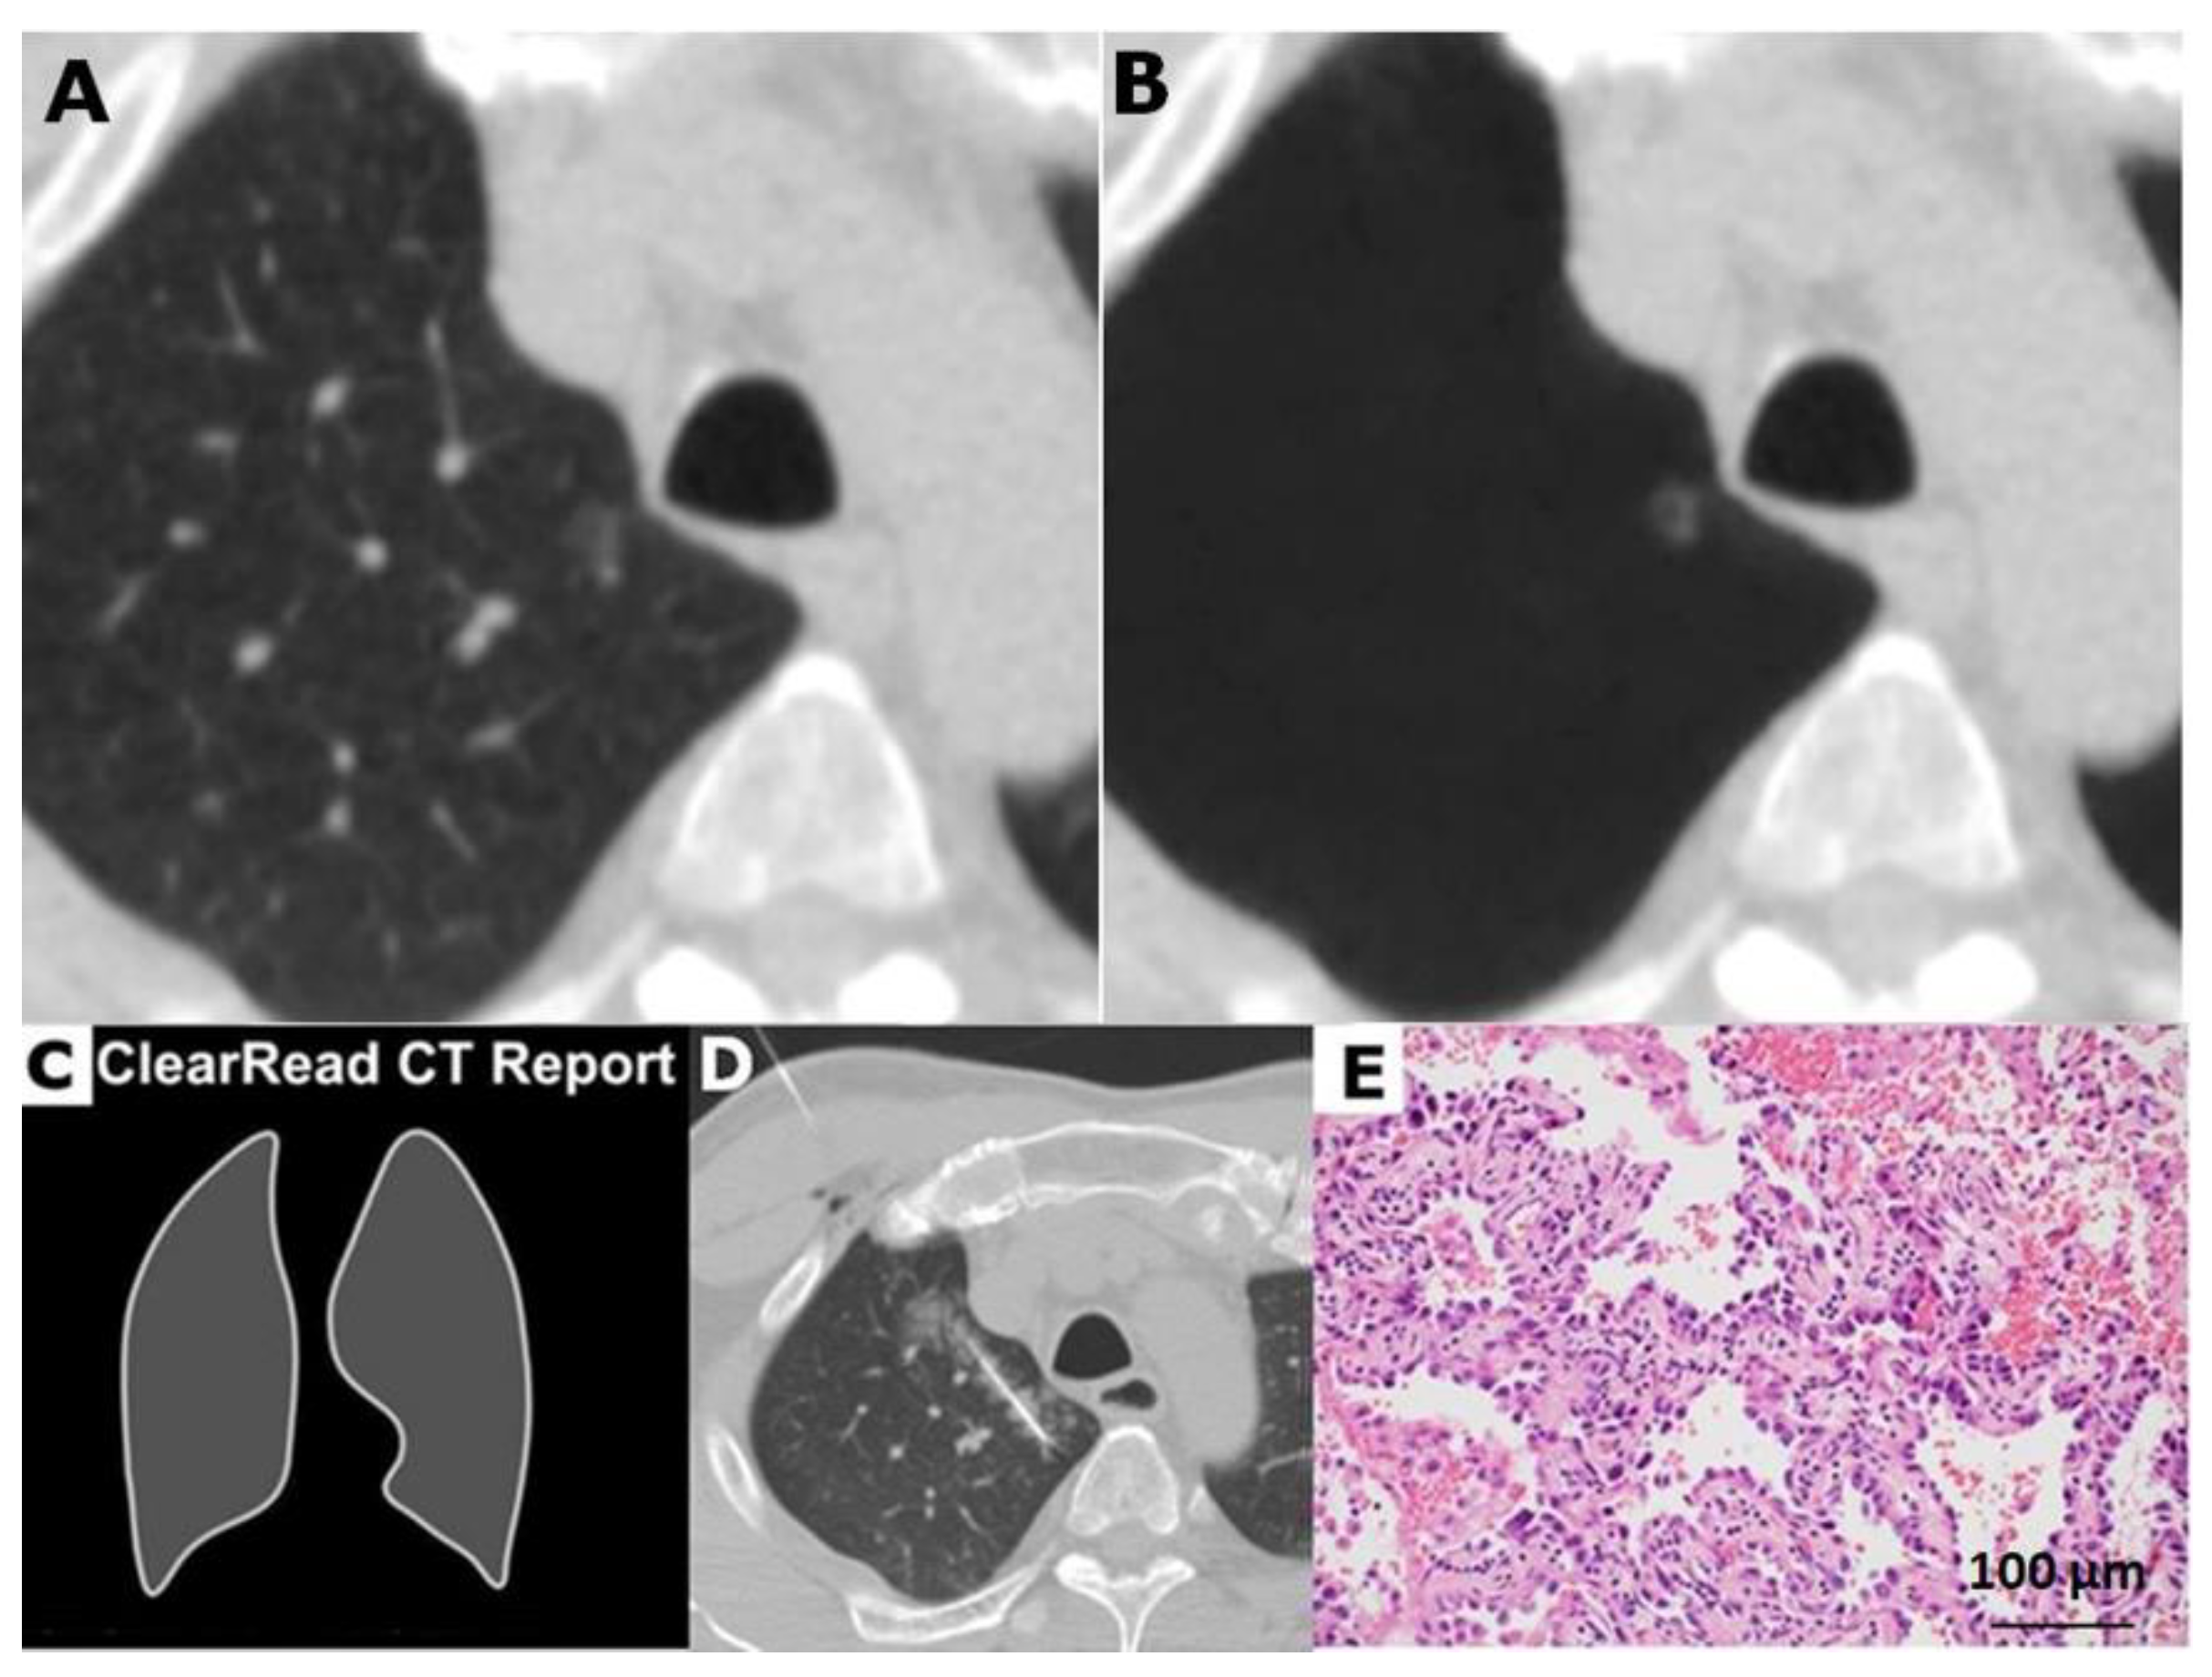

4.3.1. Vessel-Suppressed CT as VS-CAD AI Postprocessing

4.3.2. Detection and Output of CAD AI Analyzer

4.4. Lung-Nodule Characteristics and Images Interpretation